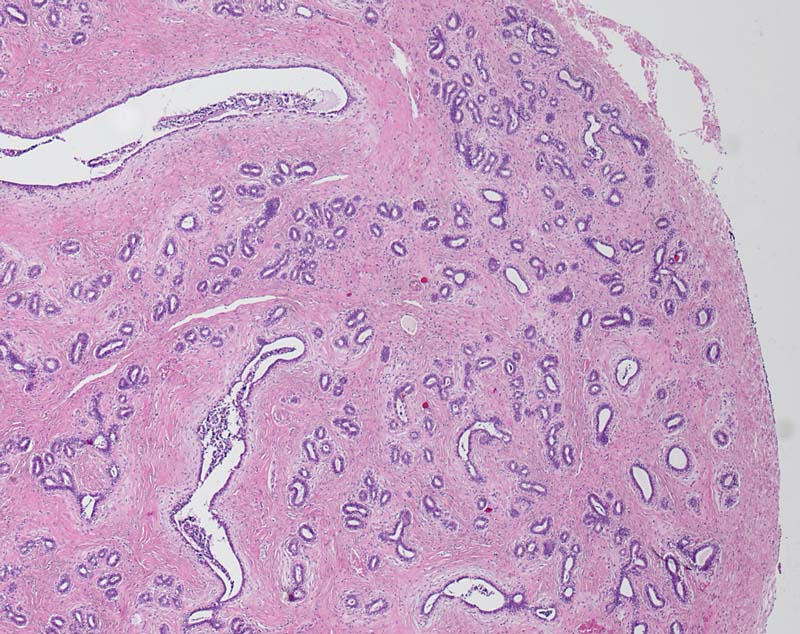

PathoPic ID 8135 - Perikanalikuläres Fibroadenom der Mamma

Perikanalikuläres Fibroadenom der Mamma

benigner Tumor

Mamma

Scharf begrenzter Tumorknoten bestehend aus bindegewebigem Stroma und glanduläre, nicht komprimierte epitheliale Elemente mit runden bis ovalären Lumina (perikanalikuläres Fibroadenom).

V. a. Fibroadenom Mamma links.

Histologie

25

21